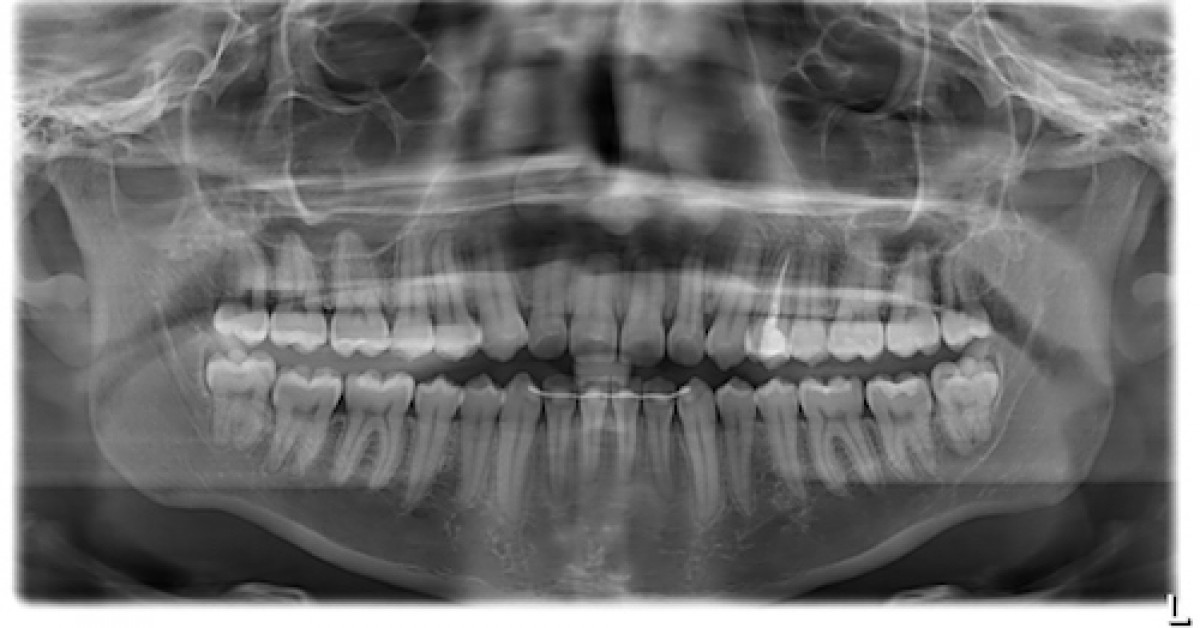

- تحلیل التهابی (Inflammatory Resorption): شایعترین نوع پس از ضربه که معمولاً با عفونت پالپی همراه است. در تصاویر رادیوگرافی به صورت نواحی شعاعی تحلیل شده اطراف ریشه دیده میشود.

- تحلیل جایگزینی (Replacement Resorption): زمانی رخ میدهد که سلولهای استخوانی به جای فیبروبلاستها وارد فضای آسیبدیده شوند. در این حالت ریشه به تدریج با استخوان جایگزین میشود (آنکیلوز). معمولاً در آسیبهای شدید مانند آولوکاسیون دیده میشود.

- رادیوگرافی دندان (X-ray): نشاندهنده نواحی تحلیل در اطراف ریشه

- CBCT (Cone Beam CT): تصویربرداری سه بعدی دقیق برای بررسی میزان و محل تحلیل